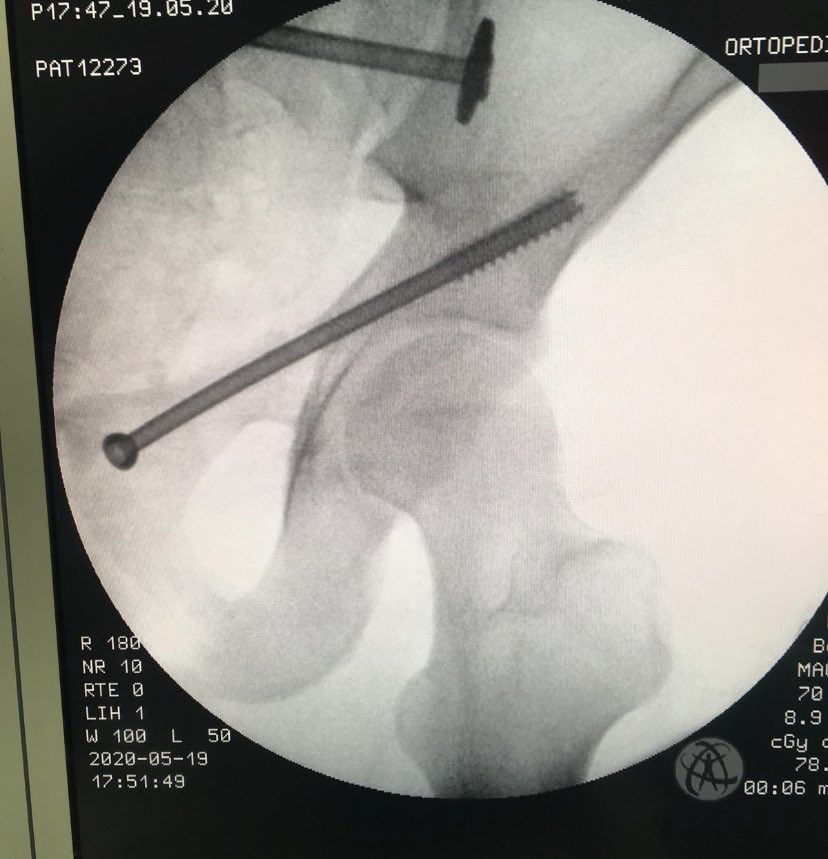

Percutaneous acetabular fixation

Dr. Diego López tweet mediaDr. Diego López tweet mediaDr. Diego López tweet media